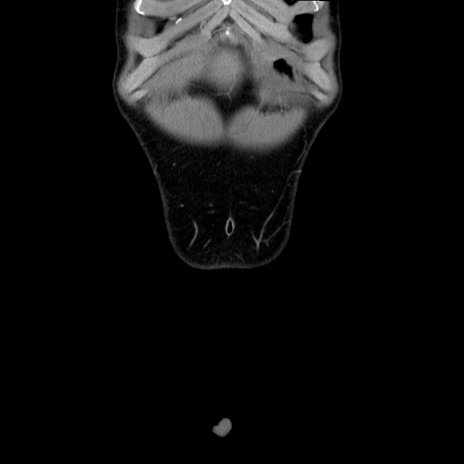

症例36(冠状断像)

【症例】20歳代 男性

【主訴】心窩部痛

【現病歴】今朝より上腹部痛あり。一旦軽快していたが再度出現したため救急要請。昨日夕に白身の魚を含む刺身を食べた。

【身体所見】BP 136/89mmHg、HR 74/min、BT 37.0℃、腹部:膨満、軟、心窩部に圧痛あり。反跳痛なし、筋性防御なし、腸雑音やや亢進あり。

【データ】WBC 17700、CRP 0.48